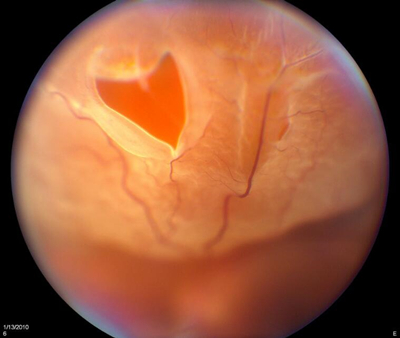

高度近视致盲并发症之视网膜脱落

由于巩膜扩张和视网膜变性,高度近视患者中得网脱的比正常人高7到8倍!幸运的是,相比青光眼、圆锥角膜,视网膜脱落还有得救,可通过冷冻、激光、镭射手术医治。当然亲们也别大意,这个要是发现得晚,没有及时医治,也是会导致永久性失明的。如果不是先天性眼睛发育异常,网脱就主要和用眼过度有关。

网脱症状:飞蚊症加重,眼前仿佛有云雾遮挡,眼球运动时有闪光感,视物变形,视力突然下降。